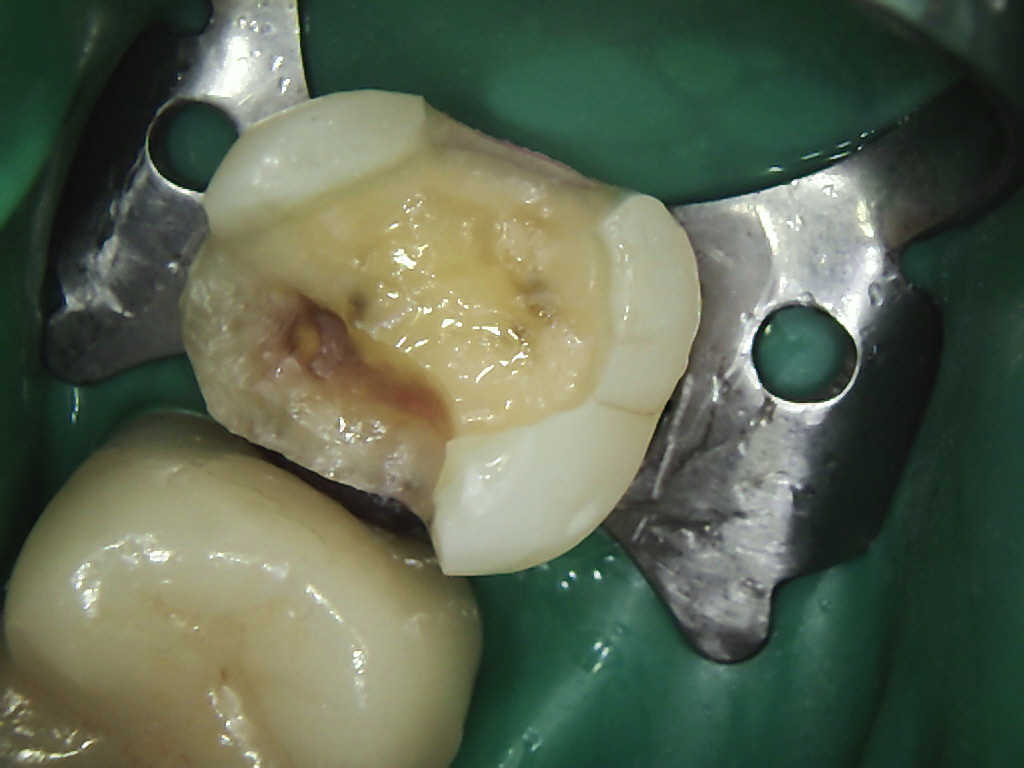

Ist der Defekt so tief, dass der Zahnnerv geschädigt wurde, so muss eine Wurzelbehandlung durchgeführt werden. Diese beinhaltet das saubere Entfernen

der Pulpa (Zahnnerv), die Desinfektion des Nervenkanals und eine bakteriendichte Füllung des Zahnes, um eine spätere Bakterienbesiedlung, welche zum Zahnverlust führen kann, zu verhindern.